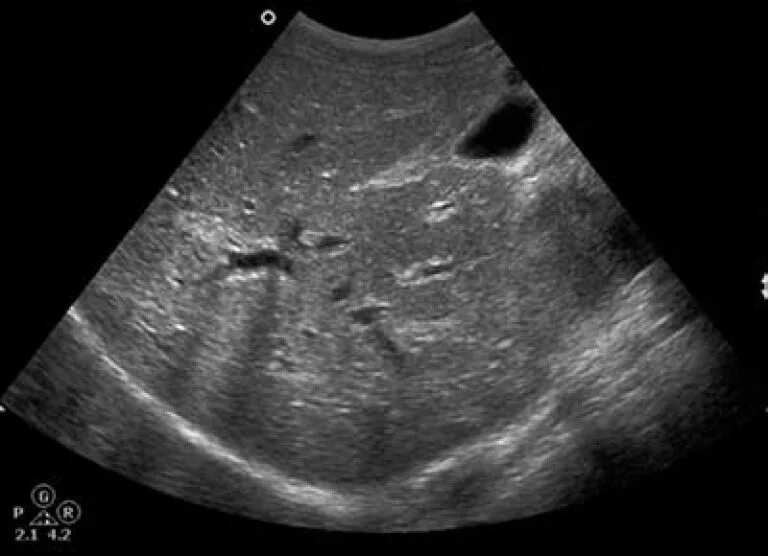

Печень увеличена на узи причины у взрослых